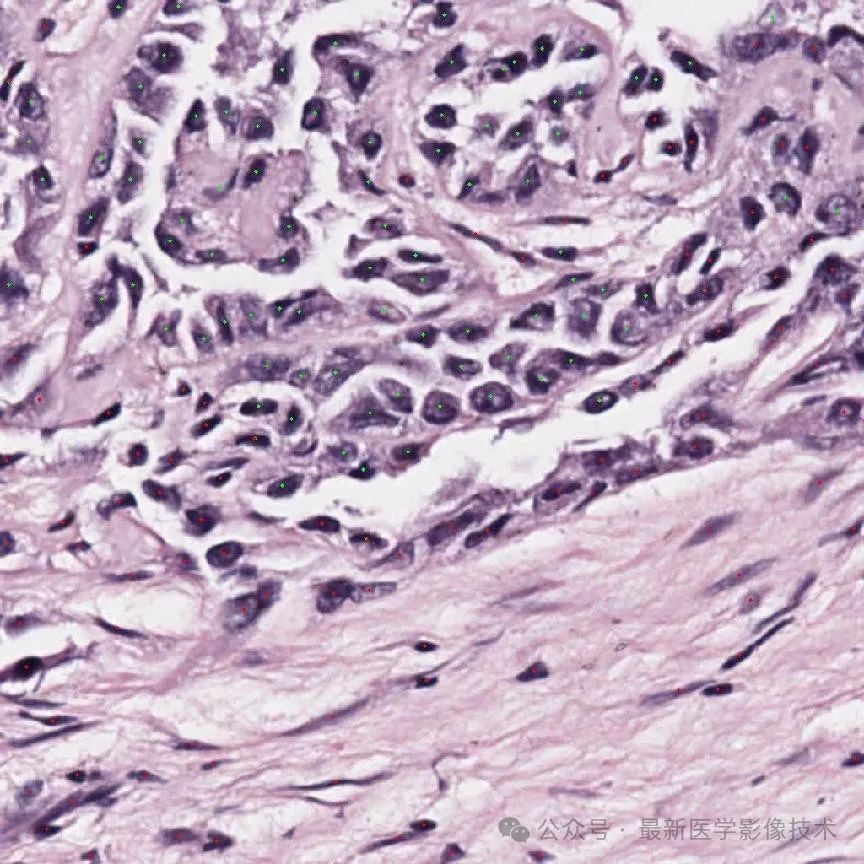

5、验证集部分分割结果

左图是原始图像,中间是金标准结果,右图是预测结果。

组织分割结果